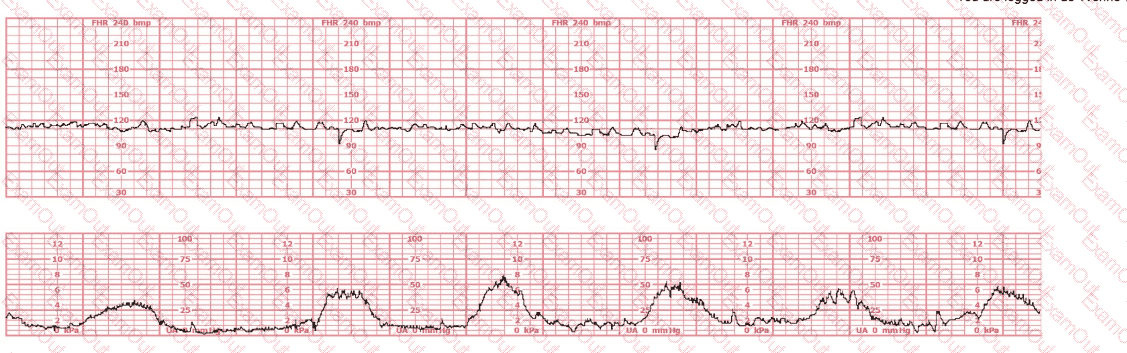

A woman is admitted to labor and delivery with vaginal bleeding. This tracing is obtained. This is most consistent with: